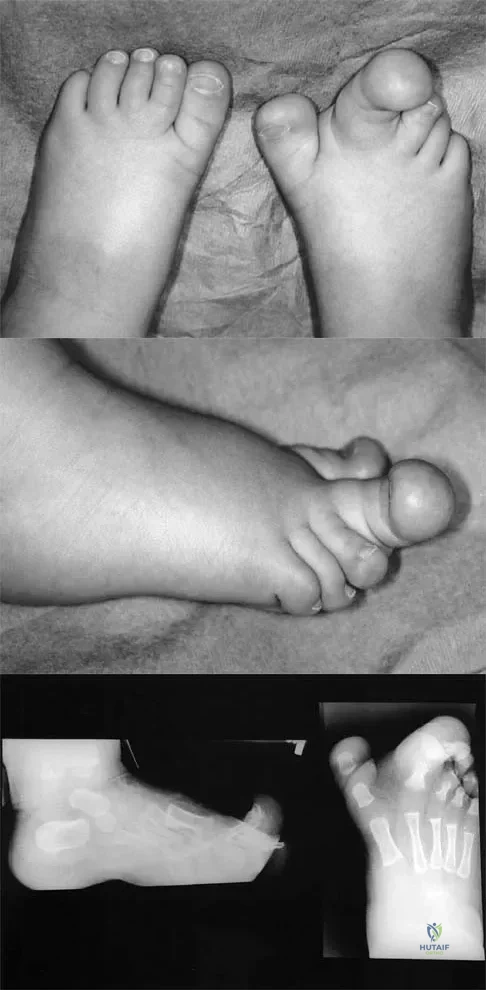

Examination of a 5-year-old boy with amyoplasia shows a flexion contracture of 70 degrees of the right knee. The active arc of motion is from 70 degrees to 90 degrees, and the opposite knee has a flexion contracture of 10 degrees. Both hips are dislocated with flexion contractures of 10 degrees, passive hip motion is from 10 degrees to 90 degrees of flexion, and the feet are plantigrade and easily braceable. Despite a daily stretching program, the parents and physical therapists note that it is increasingly difficult for him to walk because of the flexion contracture of the right knee. Management of the knee flexion contracture should now include

Most children with amyoplasia are ambulatory and when a decrease in function occurs because of a severe contracture, it must be addressed. A radical posterior soft-tissue release, including the posterior knee capsule and often the collateral ligaments and the posterior cruciate ligament, is needed to obtain extension. After the age of 1 year, aggressive physical therapy will do little to correct a contracture. Botulinum toxin A is indicated for spasticity and is contraindicated with severe contractures. Supracondylar femoral extension osteotomy works well, but will remodel at an average rate of 1 degree per month, which is not considered ideal in a young patient. Gradual correction with a circular ring external fixator is an option, but a soft-tissue release will also most likely be needed for a contracture of this severity. Sarwark JF, MacEwen GD, Scott CI Jr: Amyoplasia (a common form of arthrogryposis). J Bone Joint Surg Am 1990;72:465-469. DelBello DA, Watts HG: Distal femoral extension osteotomy for knee flexion contracture in patients with arthrogryposis. J Pediatr Orthop 1996;16:122-126.